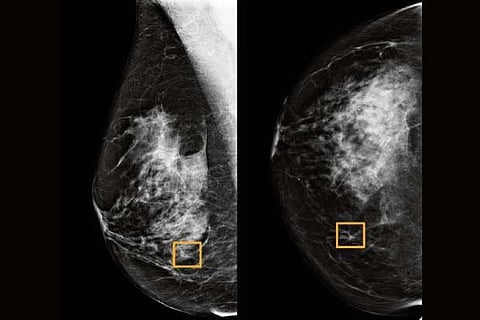

A Google artificial intelligence system proved as good as expert radiologists at detecting which women had breast cancer based on screening mammograms and showed promise at reducing errors, researchers in the United States and Britain reported.

The team, which included researchers at Imperial College London and Britain’s National Health Service, trained the system to identify breast cancers on tens of thousands of mammograms.

They then compared the system’s performance with the actual results from a set of 25,856 mammograms in the United Kingdom and 3,097 from the United States.

The study showed the AI system could identify cancers with a similar degree of accuracy to expert radiologists, while reducing the number of false positive results by 5.7% in the U.S.-based group and by 1.2% in the British-based group.

It also cut the number of false negatives, where tests are wrongly classified as normal, by 9.4% in the U.S. group, and by 2.7% in the British group.